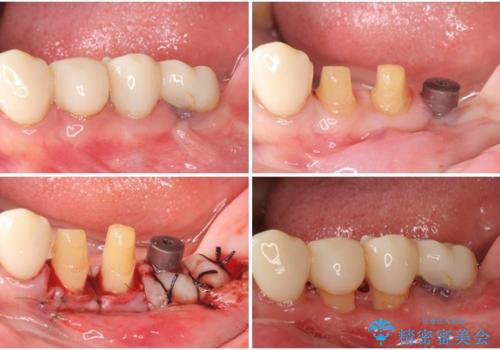

- 歯の欠損や歯肉からの出血などを気にして来院された患者様です。

診査の結果、歯周病であることが分かり、抜歯が必要な歯も見受けられました。

骨造成やインプラント、歯周外科、歯肉移植、矯正など、多くの処置を組み合わせて治療を行うこととしました。

数多くの外科処置を行ったため、治療期間は長期間となりました。

一方、外科処置をしっかりと行ったことで、歯周病の状態は改善され、安定した状態にしあげることができました。